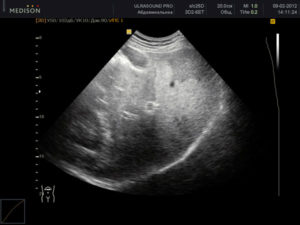

Диагноз в случае стеатоза ставится на основе инструментальных методов исследования — УЗИ печени, биохимического анализа крови. На УЗИ печень имеет «пестрый» вид за счет неравномерной структуры заполненных жирами гепатоцитов, а в анализах крови повышаются печеночные ферменты (АСАТ, АЛАТ), а также липиды крови, что отражает тесную связь между нарушением липидного обмена и стеатозом.

УЗИ печени позволяет выявить морфологические и структурные изменения органа, такие как:

- Гиперэхогенность – уплотнение тканей.

- Гепатомегалию – увеличение размеров печени.

- Жировую инфильтрацию – скопление веществ, которые в норме отсутствуют.

- Неоднородность плотности органа.

Признаки жирового гепатоза на УЗИ

При УЗИ могут быть выявлены следующие эхопризнаки гепатоза:

- уплотнение тканей печени

- увеличение размеров органа и его выход за края подреберной области

- жировое перерождение тканей печени

- неоднородность распространения поврежденных участков по органу.

УЗИ-признаки жирового гепатоза печени

Выделяют диффузную, локальную, очаговую и периферическую формы жировой инфильтрации, которые отличаются лишь распространением поражения. При диффузной форме размеры печени умеренно увеличиваются, но форма при этом не меняется.

Ультразвуковое исследование показывает снижение звукопроводимости органа, которое проявляется неотчетливой визуализацией глубоких отделов печени и диафрагмы и ухудшением визуализации мелких ветвей венозного рисунка.